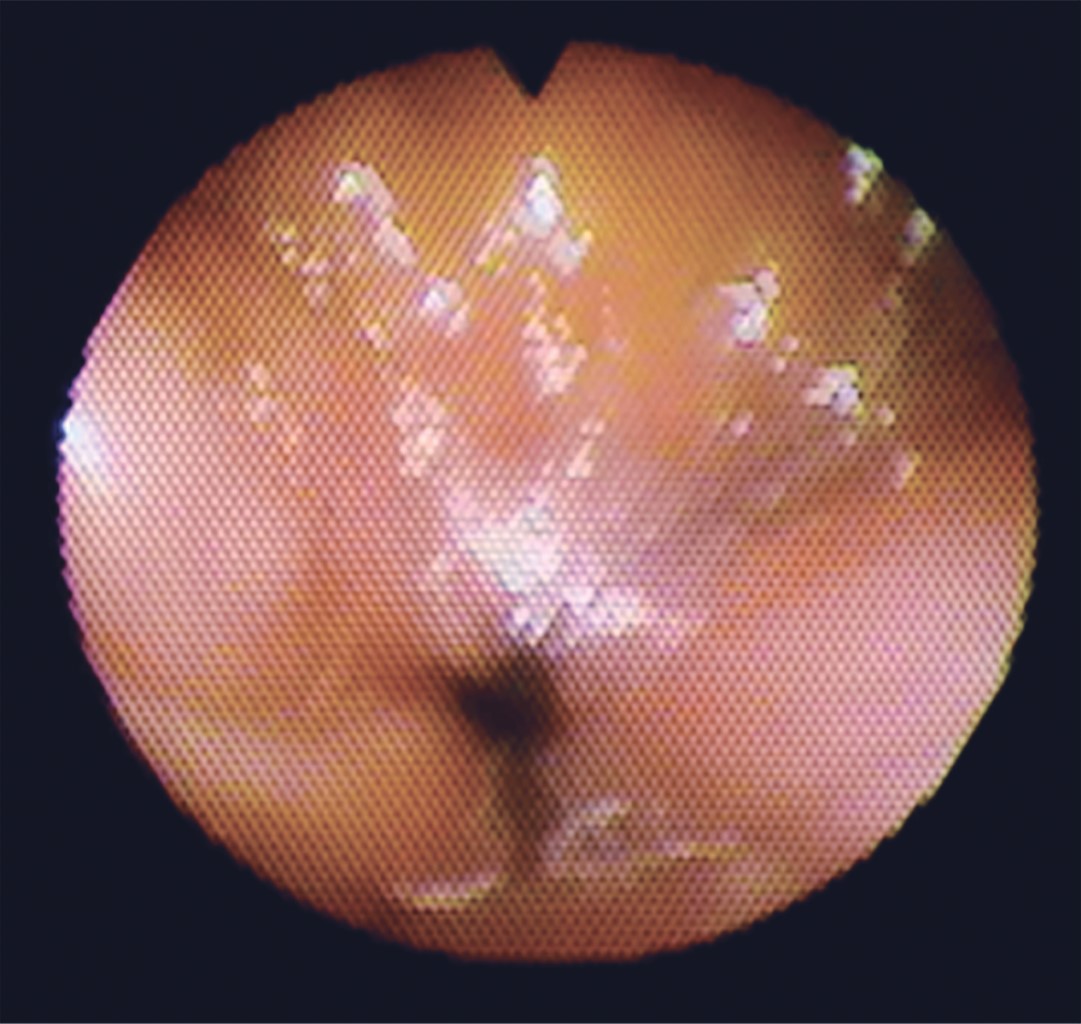

Los patrones de cierre velofaríngeo representan una descripción de una condición estática del esfínter en la fase terminal del cierre, por lo que el uso de nasofibroendoscopia es aceptado como el mejor método de análisis clínico para observar el esfínter velofaríngeo. Golding-Kushner y colaboradores,8 describieron a la nasofibroendoscopia como sistema de cuantificación y descripción de los movimientos de las estructuras del esfínter velofaríngeo, tal como se realizó en nuestro estudio obteniendo los ángulos e imágenes clínicas adecuadas para observar dicho esfínter (Figuras 5 y 6).

El patrón de cierre velofaríngeo dominante en la población mundial sin fisura palatina es el circular, los patrones de cierre velofaríngeo son categorizados de acuerdo a la pared que contribuye principalmente al cierre del esfínter velofaríngeo durante el habla. El cierre de la válvula velofaríngea es un mecanismo tridimensional que envuelve la función del velo y las paredes faríngeas, por lo que el patrón coronal ocurre cuando hay un movimiento excesivo del velo del paladar, que se desplaza a la pared faríngea posterior con menor movimiento de otras estructuras. El patrón sagital corresponde al movimiento de las paredes faríngeas laterales hacia la línea media con menor movimiento de la pared faríngea posterior y el velo del paladar. El patrón circular cuando todas las estructuras se desplazan juntas hacia la línea media y finalmente el patrón circular con rodete de Passavant, en el cual esta estructura que está formada por fibras del músculo constrictor superior de la faringe contribuye al cierre en la línea media (Figura 1).3,5,7,8,17,20